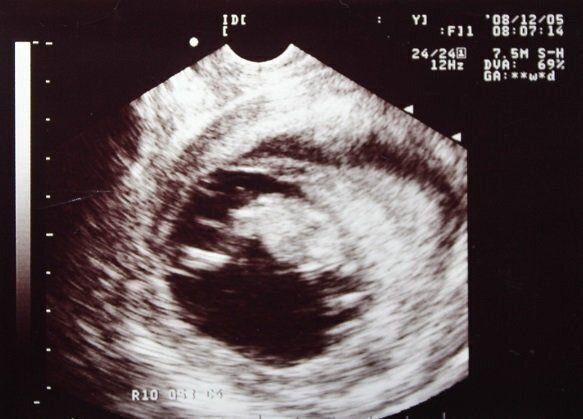

総合病院で再度、詳しい検査を行いました。そして、この出血は「絨毛膜下血腫」が原因だと判明したのです。エコーで赤ちゃんの心音を聞かせてもらうと、「生きているよ!」と、私に訴えているように感じました。

エコー画像には、赤ちゃんの入っている袋よりもはるかに巨大な「血だまり」が、真っ黒な影として写っていました。この子宮内の血液は徐々に外に出ていくか、次第に子宮内に吸収されるものもある。今できる治療は、入院して子宮の収縮を抑える薬と抗生物質を点滴しながら、安静にすることだけだと医師から説明されました。